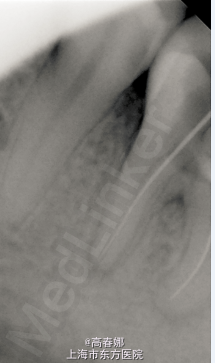

主诉:左下后牙咬物隐痛一月余。 现病史:患牙数年前于外院行“烂神经”治疗,近一月余自觉咬物酸痛不适就诊。 既往史:无特殊。

检查:36充填物完好,扣诊(+),无松动,牙龈无明显红肿,冷诊(-)。 X线示:髓腔内高密度阻射影像,根尖区阴影。

诊断:36慢性根尖周炎 处理: 一诊:36去除牙合面积髓腔内原充填物,探及近中颊舌根及远中根三根管,拔除坏死牙髓,近中两根管细小,10#及15#根管扩大锉疏通根管,双氧水及生理盐水交替冲洗根管,干燥,髓腔内置FC棉球,暂封,告常规医嘱,肿痛随诊。 二诊:一周后复诊,无不适主诉。查36扣诊(-),牙龈无红肿,FC棉球无臭味,无明显渗出。36去除暂封及FC棉球,手用PROTAPER SX锉预备根管中上1/3,根管长度测量,WAVE-ONE完成根管预备,预备过程中双氧水及生理盐水交替冲洗根管,干燥,髓腔内置FC棉球,暂封,告常规医嘱,肿痛随诊。 三诊:一周后复诊,无不适主诉。查36扣诊(-),牙龈无红肿,FC棉球无臭味,无明显渗出。36去除暂封及FC棉球,根充糊剂+大锥度牙胶尖侧压充填,X线示适充,锌基,树脂充填,调合,抛光,告常规医嘱。建议观察一至二周全冠修复。